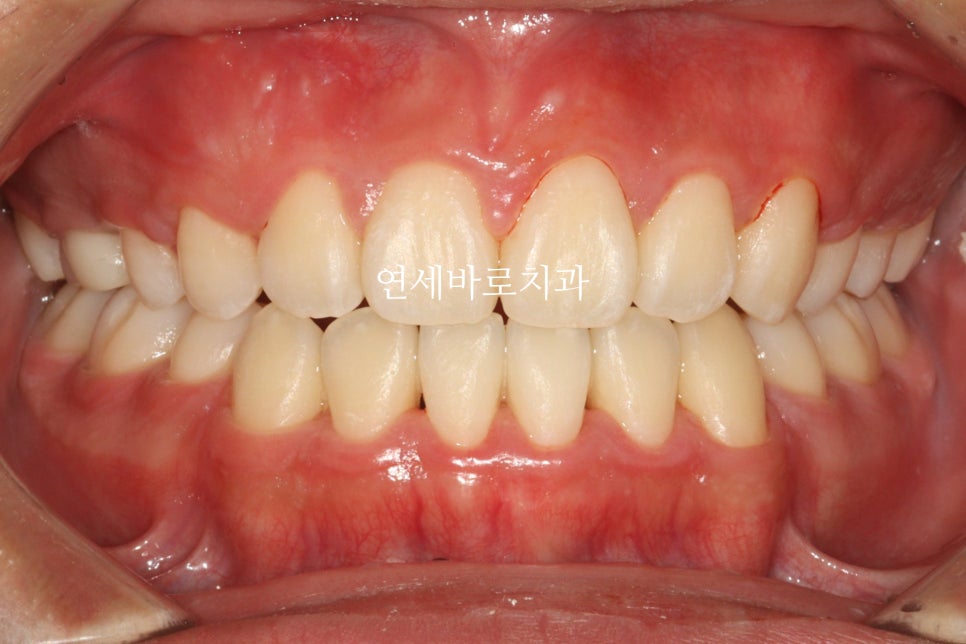

그리고 24.6. 교정을 시작한지 약 1년 반정도만에 치료가 마무리 되었습니다.

송곳니를 발치함으로 얻은 이득 중 하나는 '치료기간'입니다.

치료기간이 엄청 짧아진거죠.

단점은 좌우 대칭이 아니라 약간의 심미적인 문제가 생기는 것입니다.

그 심미적 문제가 이것입니다.

화면의 왼쪽은 작은 어금니

오른쪽은 송곳니 입니다.

그래서 모양이 다르죠.

이런문제가 있긴 하지만 거의 티가 나진 않습니다.

전과 후를 비교하며 작성을 마치겠습니다.